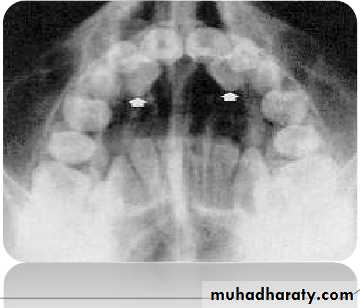

OPG

Panoramic radiographs are basic radiograph

for assessment of impacted teeth•

•

Tooth position whether deep or shallow

General orientation horizontal or inclined

mesially/distallyRelationship with neighbouring teeth

Risk of their transpositionPresence or absence of apical resorption of

roots of adjacent teeth

53

When mesio distal width of canine crown was

1.5 times larger (i.e. 15% larger) than theadjacent central incisor, then the canine is

palatally placed

This is only true in cases where canine should

not be at a higher level55

Ericson and Kurol in EJO 1988 defined number of

sectors to denote different types of impaction.

i.

ii.

Sector 1: if the cusp tip of the canine is

between the interincisor median line and the

long axis of the central incisor;

Sector 2: if the peak of the cuspid of the canine

is between the major axes of the lateral andcentral;

iii. Sector 3: if the peak of the cuspid of the canine

is between the major axis of the lateral and thefirst premolar.